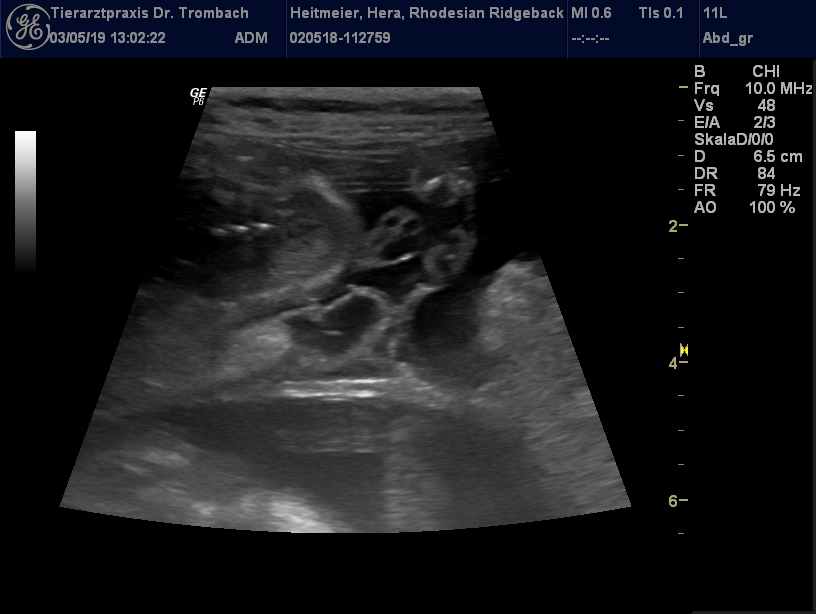

waren bei unserer Ärztin und haben nochmals geschallt...

8 kleine Früchtchen konnte Sie erkennen!